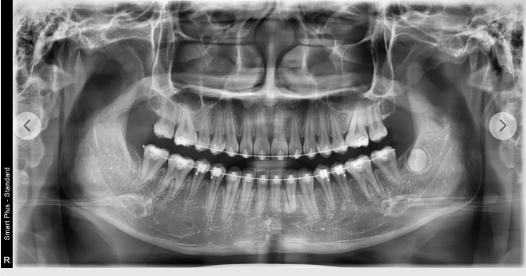

1. 정밀 진단

눈으로 보는 것에 그치지 않고, 엑스레이와 CT를 통해 턱뼈의 위치, 치아의 각도, 턱관절의 상태를 입체적으로 분석했습니다.

이 환자분의 경우, 하악골이 상대적으로 발달하여 얼굴이 길어 보이는 골격성 부정교합이었습니다.